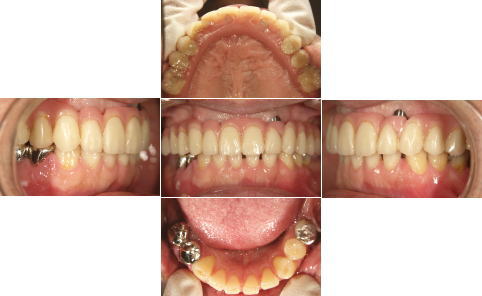

| 上顎はいつ抜けてもおかしくない状態であったため、直ちにAll-on-4を施術しました。 下顎も重度の歯周病で状態は良くありませんでしたが、患者様の希望もあり、抜歯せず、現在経過観察中です。 |